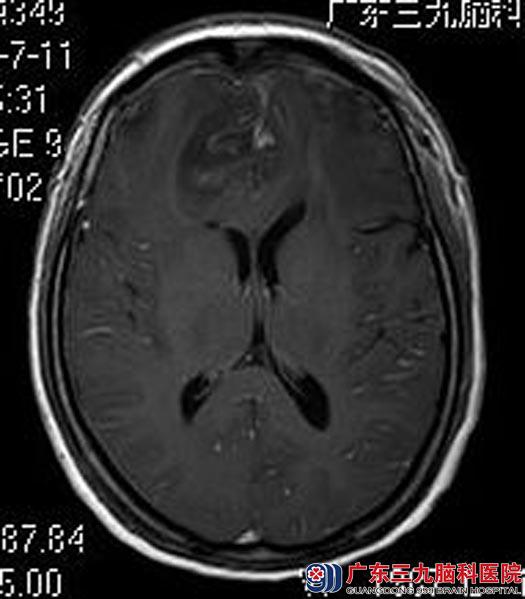

由鲁明主任主刀,在全麻下行双侧额部大脑镰旁巨大脑膜瘤切除术,术中见肿瘤质硬,包膜完整,血供一般,显微镜下行肿瘤全切,手术顺利,术后陈女士恢复很快,已康复出院。术后病理结果:纤维型脑膜瘤(WHO I级)。